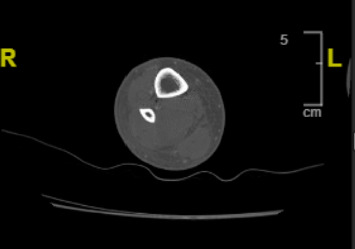

急性筋膜室综合征是由于封闭筋膜间隙内压力增加而引起的一种医学紧急情况,如果不治疗,可导致组织缺血和潜在的肢体丧失或死亡。虽然通常继发于创伤,但罕见病例与链球菌感染有关。然而,没有文献记载的病例室综合征起源于A群链球菌(GAS)咽炎。我们提出一个35岁的女性,糖尿病前期,谁提出了恶化的右下肢(RLE)疼痛和水肿后,发热性疾病与咽炎急诊科。入院时咽拭子和随后的血液培养均检测出溶血气体呈阳性。尽管最初治疗败血症和蜂窝织炎合并肌炎,但她出现了筋膜室综合征,需要紧急切开筋膜。她术后出现低血压、中毒性休克样综合征、月经过多和转氨炎,但最终通过静脉注射抗生素和逐步进行雅各梯手术缝合伤口恢复。该报告是已知的第一例由弥散性气体咽炎引起的非创伤性急性下肢筋膜室综合征,并可能指出美国新出现的气体毒株的新毒力因子的发展。该病例强调了认识到气体性咽炎作为严重全身性感染的潜在来源的重要性,因为早期发现和积极治疗侵袭性气体性感染可能有助于预防危及生命的并发症。

Acute compartment syndrome is a medical emergency caused by increased pressure within a closed fascial space, leading to tissue ischemia and potential limb loss or death if untreated. While typically secondary to trauma, rare cases have been associated with streptococcal infections. However, no documented case exists of compartment syndrome originating from Group A Streptococcus (GAS) pharyngitis. We present a 35-year-old female, with prediabetes, who presented to the emergency department with worsening right lower extremity (RLE) pain and edema following a febrile illness with pharyngitis. Throat swab on admission and subsequent blood cultures tested positive for beta-hemolytic GAS. Despite initial management for sepsis and cellulitis with myositis, she developed compartment syndrome requiring urgent fasciotomy. Her postoperative course was complicated by hypotension, toxic shock-like syndrome, menorrhagia, and transaminitis, but she ultimately recovered with IV antibiotics and stepwise Jacob's Ladder surgical wound closure. This report serves as the first known case of nontraumatic acute lower extremity compartment syndrome derived from disseminated GAS pharyngitis and may point to the development of novel virulence factor(s) for emerging strains of GAS in the United States. The case underscores the importance of recognizing GAS pharyngitis as a potential source of severe systemic infections, as early identification and aggressive management of invasive GAS infections may help prevent life-threatening complications.